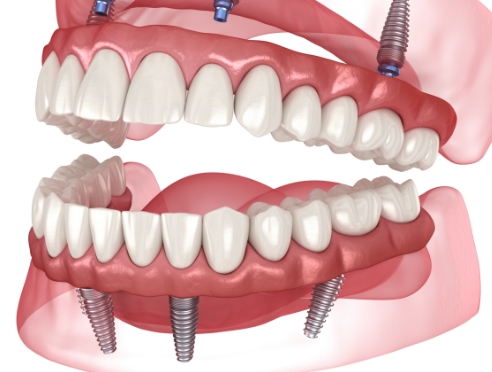

通过种植牙, 让您无忧进食, 自在微笑, 重拾生活的舒适感

种植牙是一项高难度治疗,

需依赖精密检查与充分的术前计划

因此, 选择具备丰富经验与专业技术的

医疗团队尤为重要